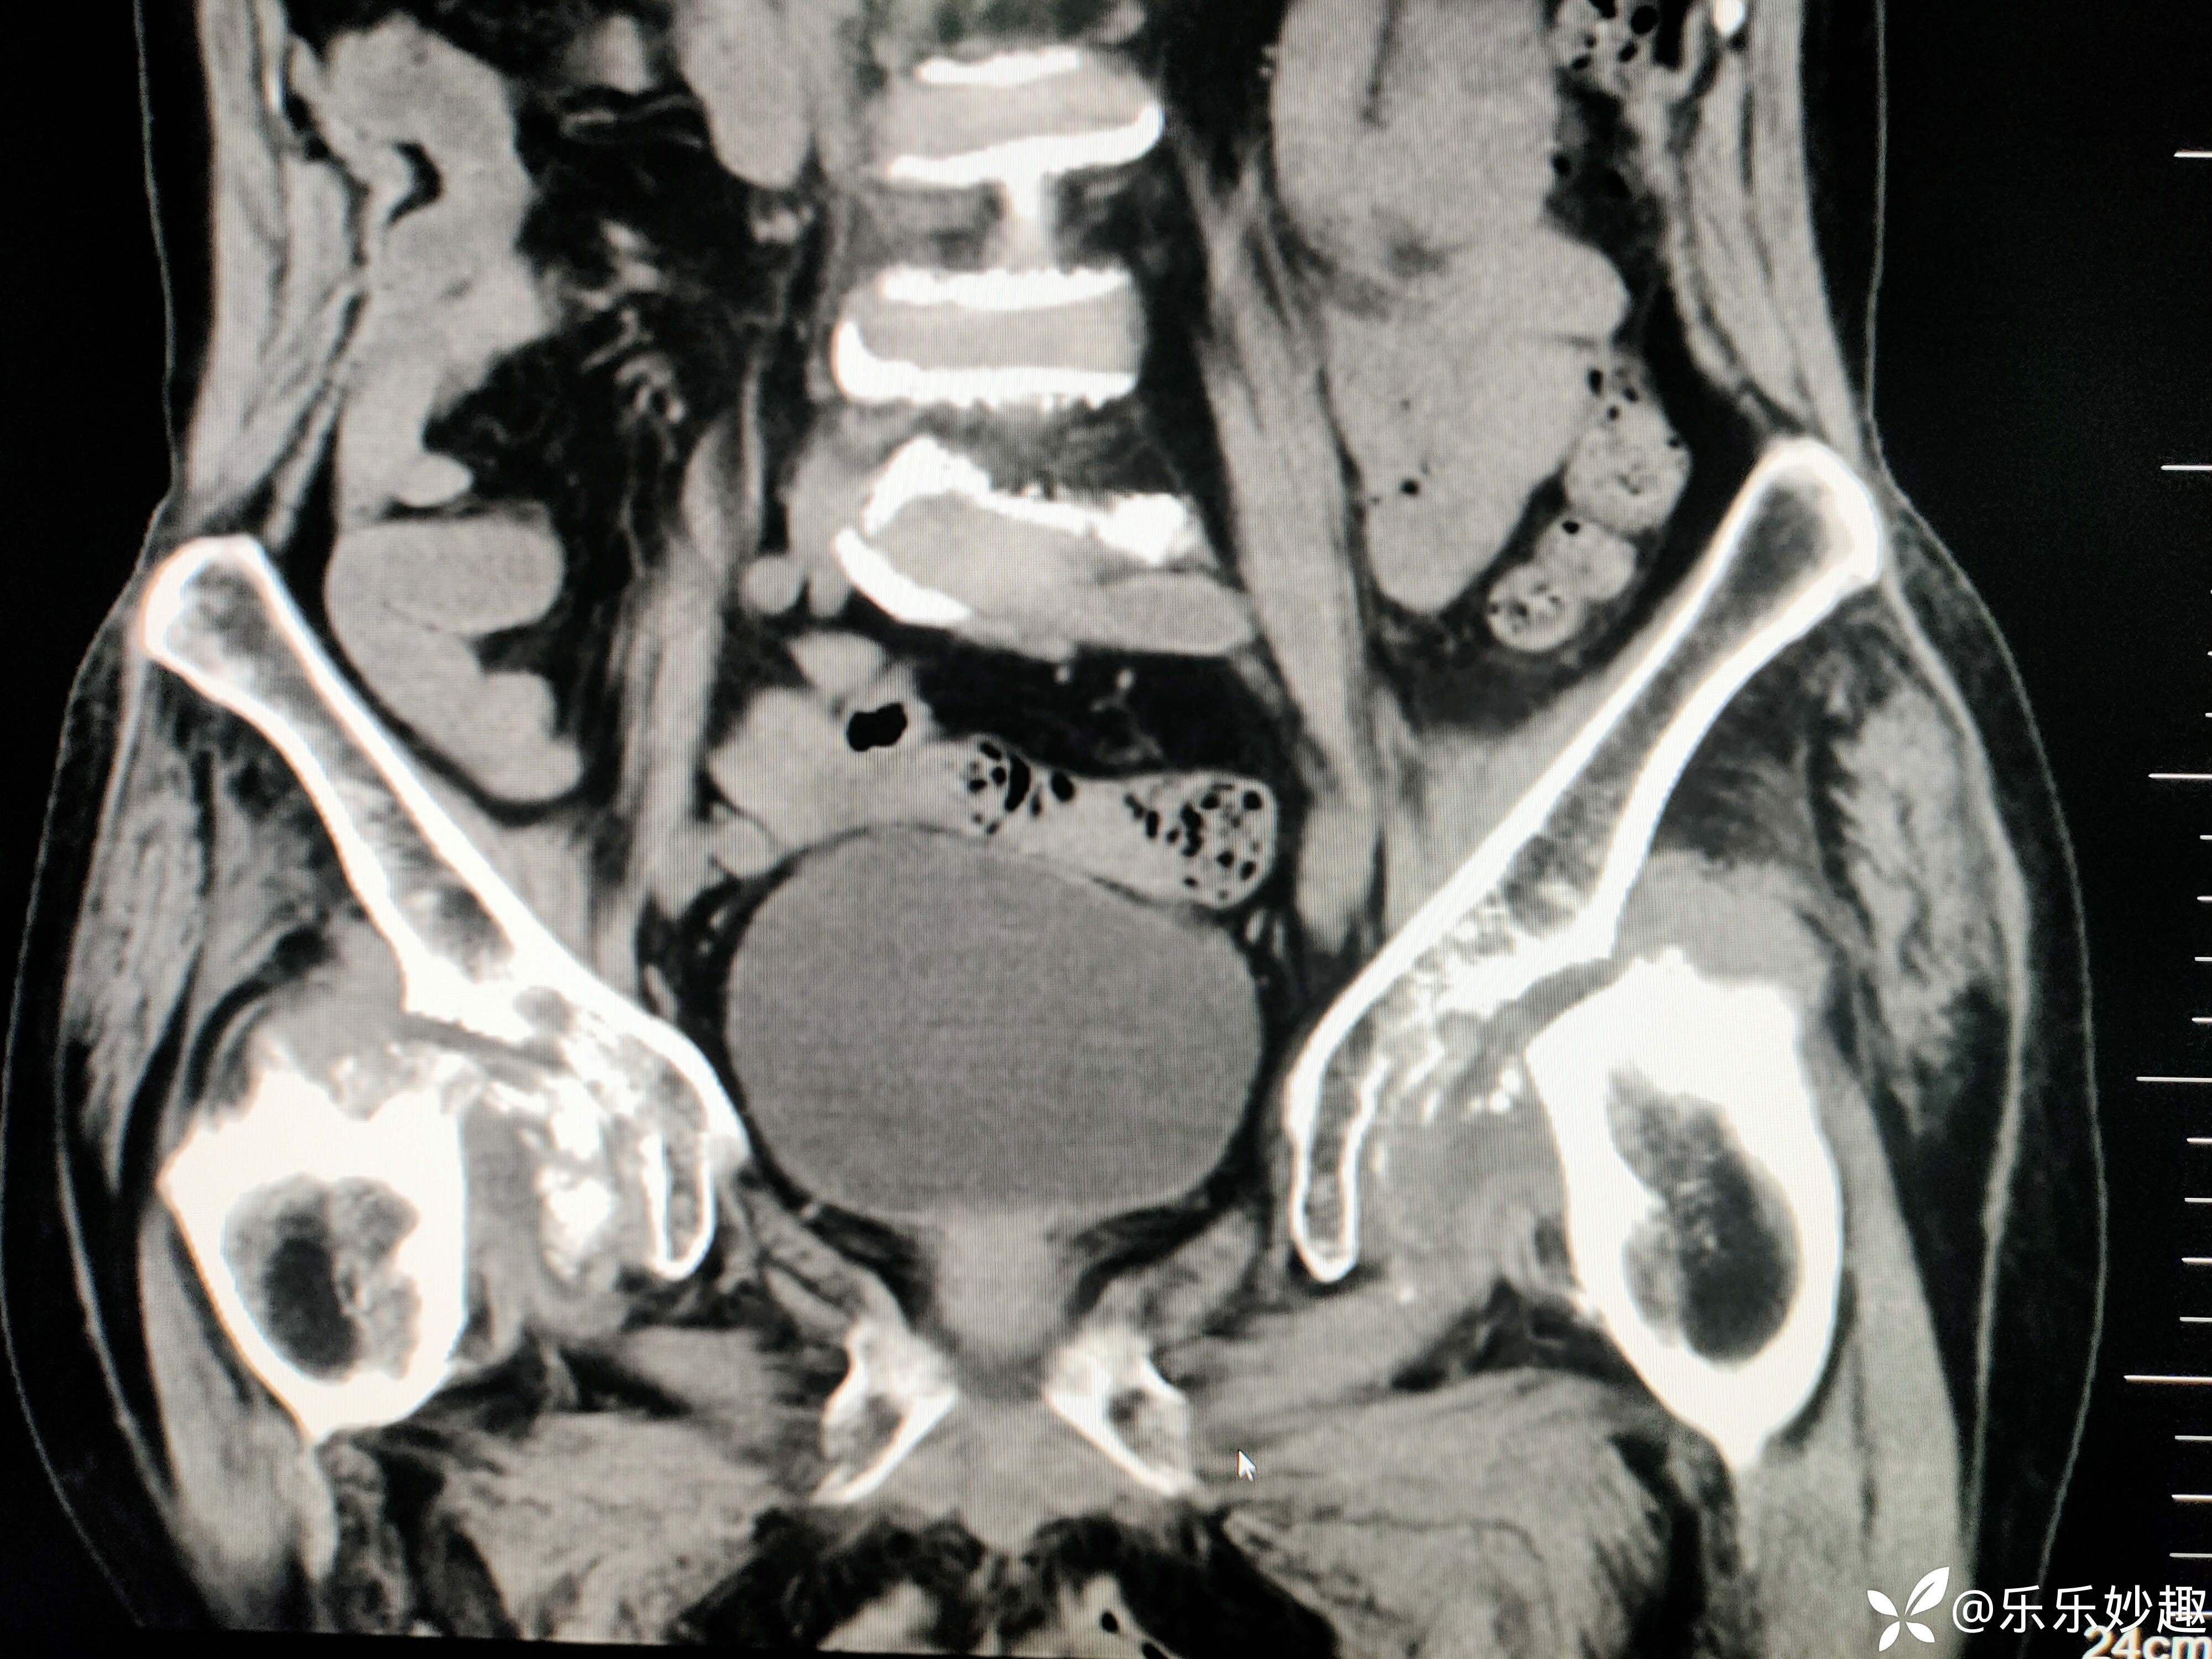

最后做了髋关节MR,见下图